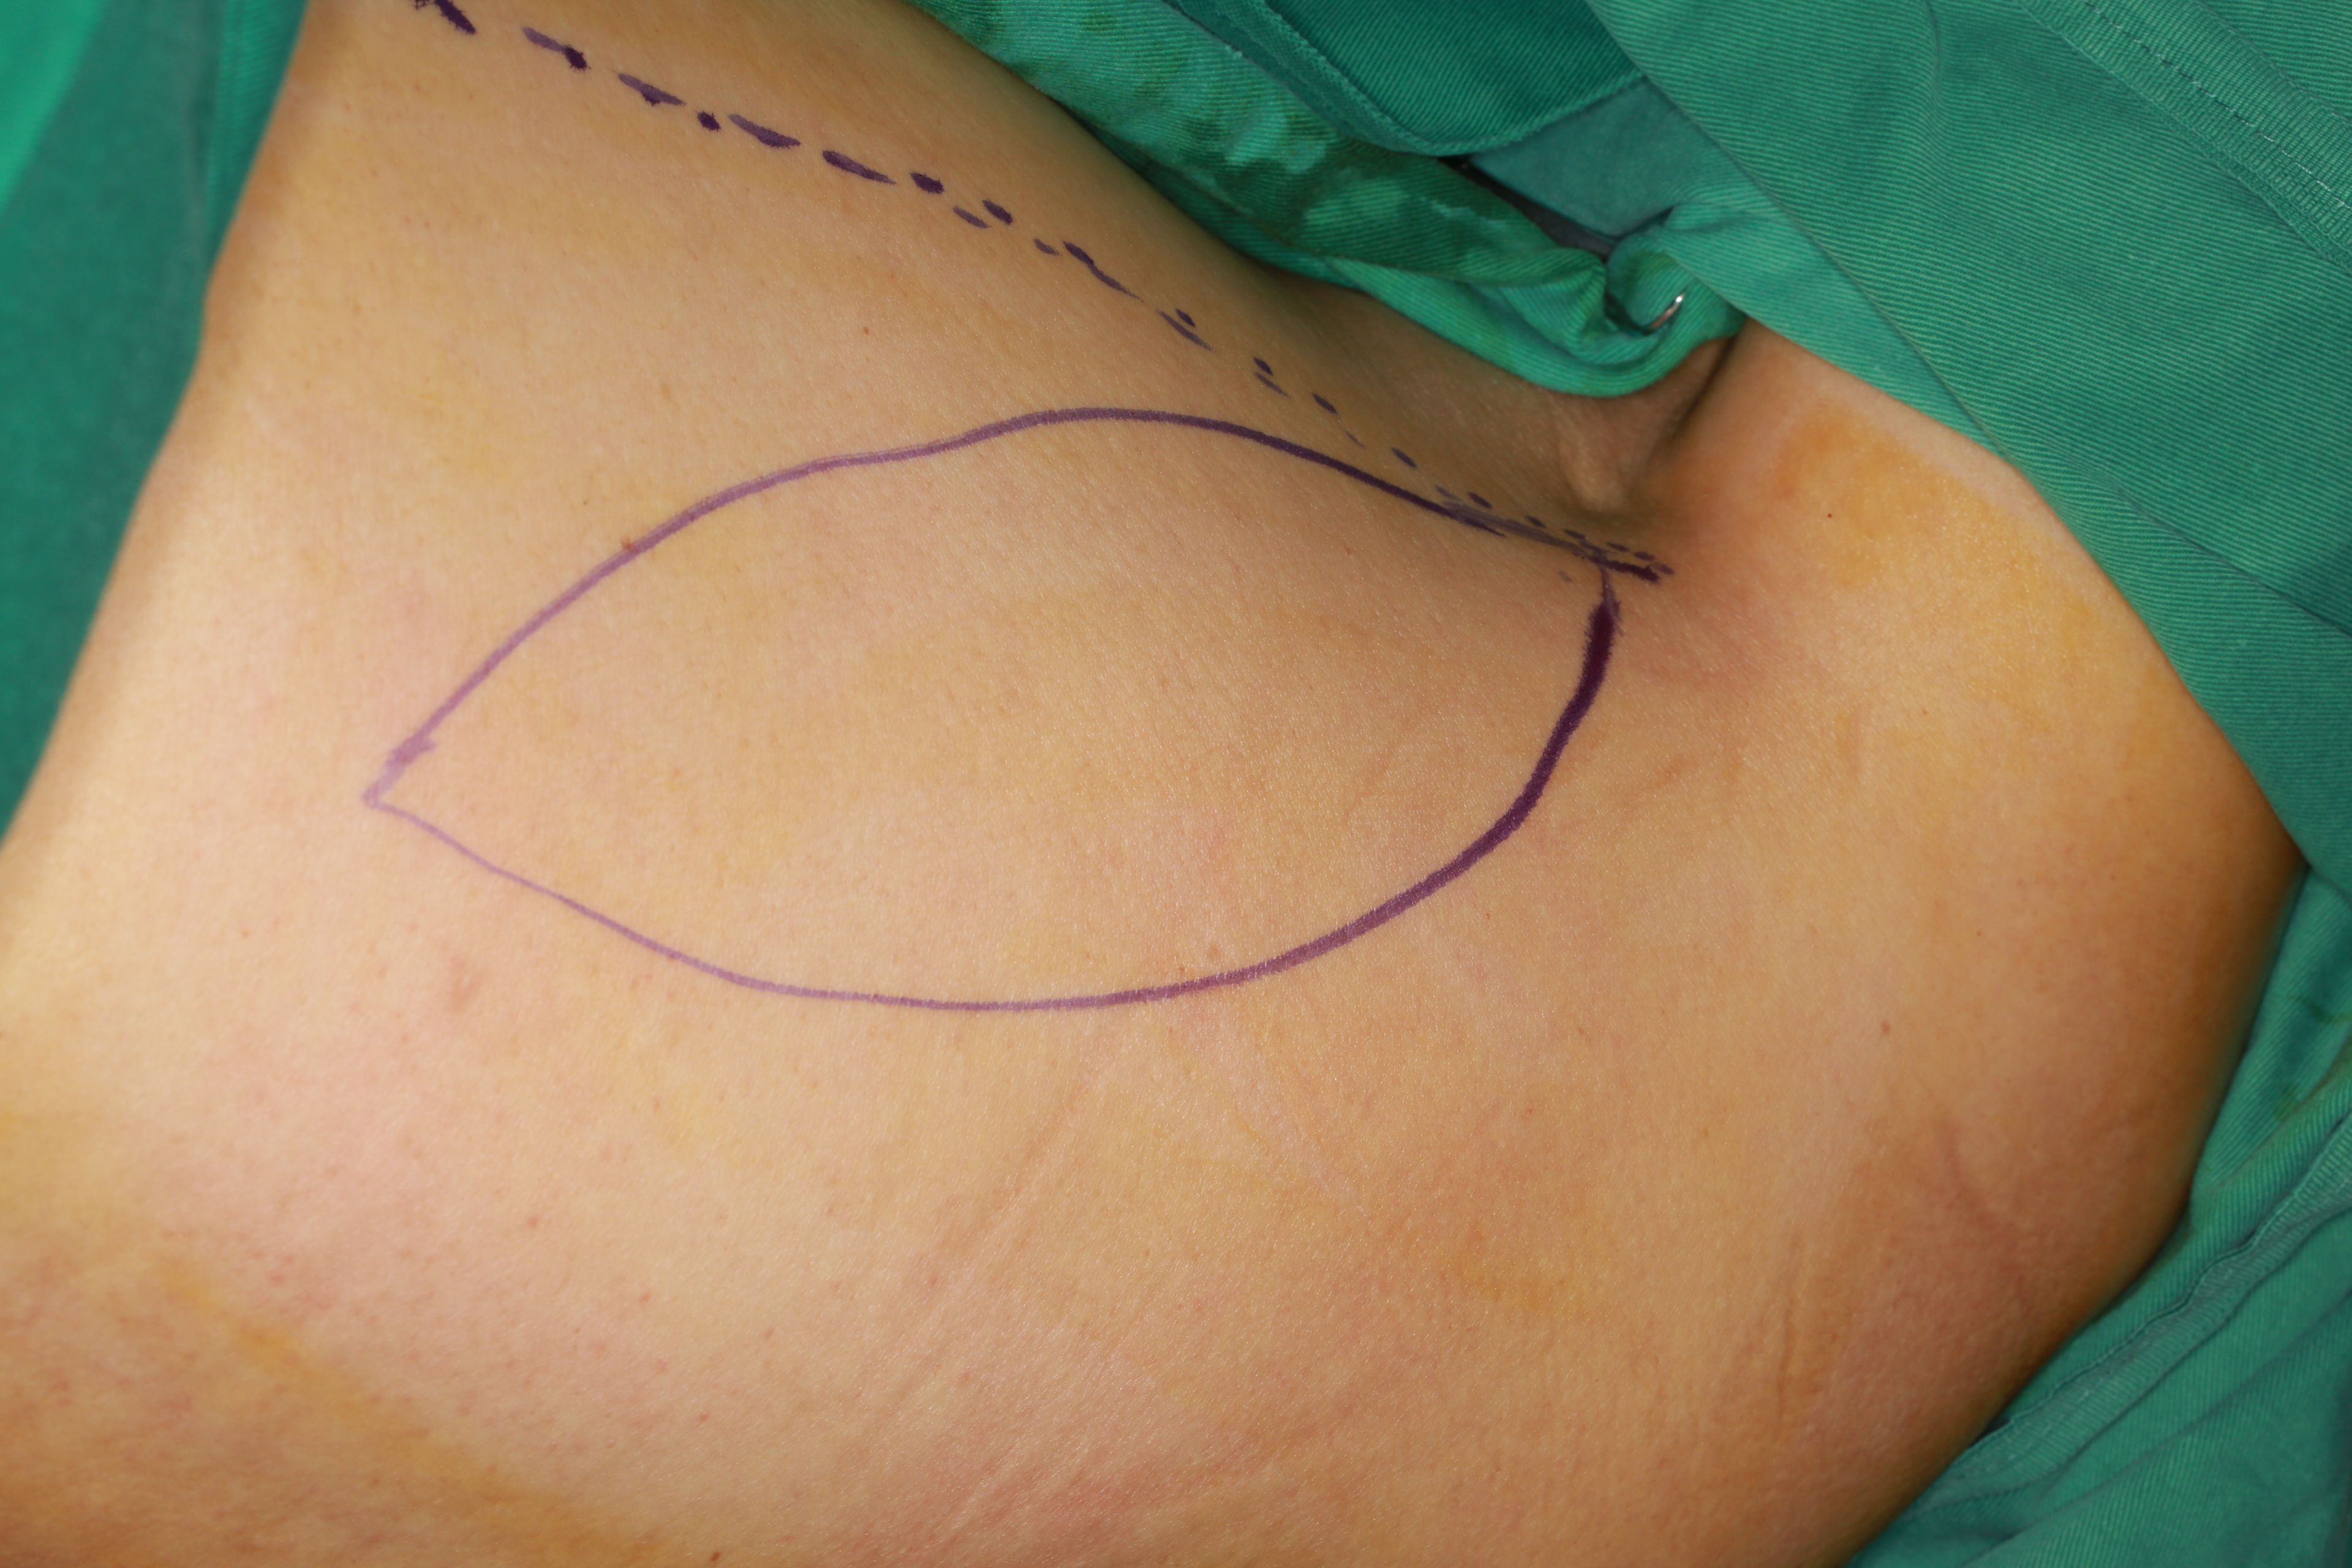

一、头颈部恶性肿瘤的综合治疗以及恶性肿瘤治疗后功能整复。针对各类口腔癌,尤其是中晚期口腔癌指定的个性化治疗方案。在进行肿瘤根治性治疗的基础上同期利用各种游离组织瓣移植修复完成缺损的一期修复。(图为前臂皮瓣与背阔肌皮瓣术前设计)